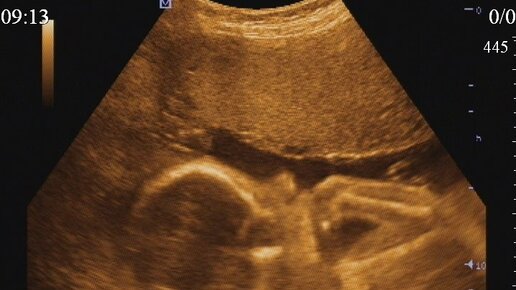

Если раньше пол определяли по форме живота, то сегодня современные методы диагностики позволяют максимально точно определить, кого ждать: мальчика или девочку. Но даже не смотря на то, что сейчас есть и 3D и даже 4D-УЗИ, иногда врачи неверно определяют пол ребенка. Ошибаются чаще всего на 1 скрининге, ведь в 12-13 недель предположить, сын у вас или дочка, может только очень опытный специалист, а в большинстве случаев про пол вообще ничего не говорят. После 16 недель и на 2 скрининге вероятность ошибки минимальна - половые органы малыша уже полностью сформированы...